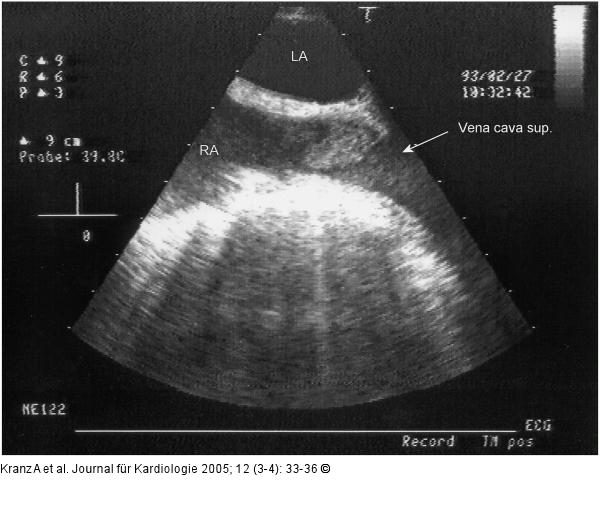

Abbildung 3a-b: Vena cava sup. - Subtotale Thrombose |

Abbildung 3a

Abbildung 3a-b: Vena cava sup. - Subtotale Thrombose